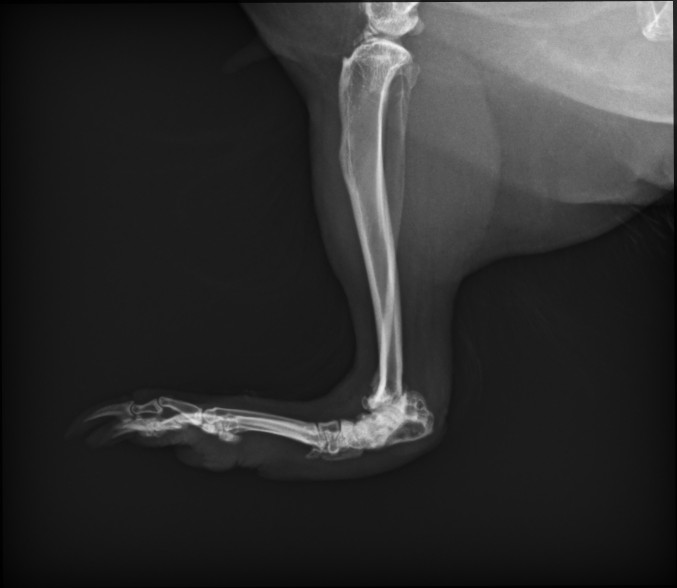

• Ich habe heute von Helga die Röntgenbilder bekommen. Zudem habe ich eine Physiotherapeutin gefunden. die sich an Schweinchen mal ausprobieren würde. Helga kommt mittlerweile mutig her und nimmt Futter gerne. Nur die Medis muss ich noch reinschmuggeln. Sie läuft auch deutlich besser und mehr. Ihr Schilddrüsenwert war tatsächlich mit 0,9 unter dem Grenzwert von 1,1 (Ich weiß die Einheit leider nicht). Da das ja alles nicht so eindeutig ist fordert die Tierärztin nochmal einen Wert nach und wir kontrollieren in 4-6 Wochen und stellen sie dann bei Bedarf ein.

Die Röntgenaufnahmen würde ich gerne besser verstehen:

Auf der zweitletzten Aufnahme ist das Sprungelenk m.E. klar als das zu sehen, was bei uns Menschen im Bereich der Ferse wäre. Etwas weiter links davon das dunklere ist dann vermutlich der Mittelfußknochen?

Du hattest geschrieben, dass Ihr Sprunggelenk stark geschädigt ist. Aber sieht es auf dem letzten Bild nicht so aus, als sei auch der Mittelfußknochen kaputt?

Es freut mich auch, dass wir ihr helfen konnten. Vielleicht nicht ursächlich oder so, aber zumindest die Schmerzen nehmen. Sie streckt beim Schlafen auch nicht mehr so übertrieben die Beinchen weg, vielleicht war das doch ein Zeichen von Entlastung.

Den hatte ich glatt übersehen. Ich könnte mir vorstellen, dass die Ärztin mit Sprunggelenk den Teil eingeschlossen hat, da der gesamte Bereich falsch ausgebildet ist. Weißt du, was ich meine? Ich habe leider gerade unsere anderen Röntgenbilder von Füßchen nicht zur Hand um das zu vergleichen.